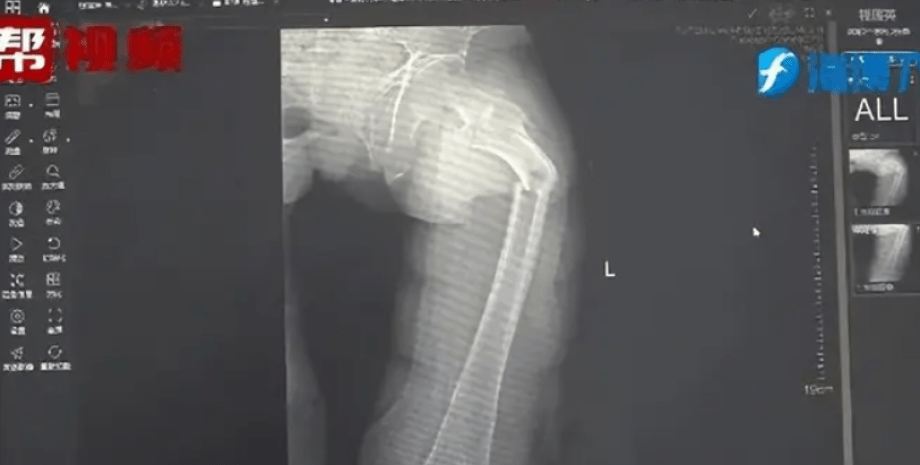

У Китаї 35-річний чоловік зламав стегнову кістку, найміцнішу кістку в людському тілі, просто під час кашлю. Про незвичайний випадок повідомили лікарі Другого народного госпіталю провінції Фуцзянь, пише Oddity Central.

Рентген показав, що у пана Є перелом стегнової кістки. Його історія про кашель не відповідала жодним фізичним травмам. Лікар Чжун та його команда вирішили провести додаткове обстеження. Вони розпитали пацієнта про його загальний стан здоров'я, харчові звички та спосіб життя, а також провели тест на щільність кісткової тканини, який продемонстрував тривожні результати. Показники 35-річного чоловіка відповідали нормі 80-річного. Ці результати є незвичними навіть для сучасних малорухливих людей.